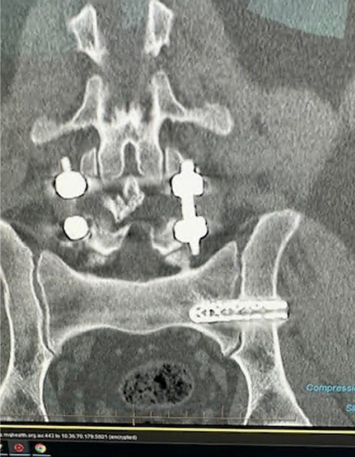

A 75-year-old woman developed right-sided buttock, groin, and leg pain 33 years after an L5/S1 fusion. MRI was limited by artifact, CT showed no major compression, and SIJ injection produced excellent relief.

This revision case had already gone through a cluneal nerve stimulator, cluneal nerve radiofrequency ablations, repeat SIJ injection, and repeat SIJ ablation before robotic and endoscopic revision planning was considered.

A 21-year-old active gymnast with hypermobility, several years of back pain, and severe SIJ tenderness underwent multiple prior treatments before robotic sacroiliac joint fusion led to good pain improvement and return to reasonable normal activity.